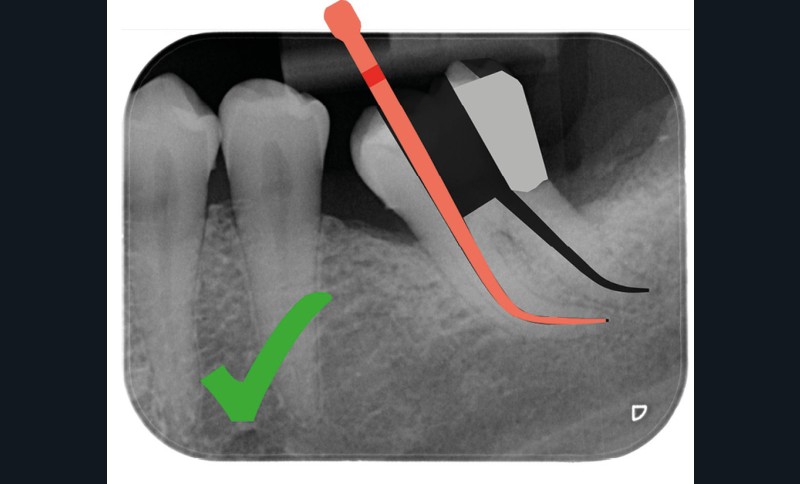

Une cavité d’accès trop petite [2] optimiserait le pronostic biomécanique (préservation dentaire maximale) mais pourrait compromettre le pronostic endodontique : mauvaise lecture de l’anatomie, instrumentation partielle, non ergonomique et avec risque de fracture, défaut de nettoyage des parois canalaires [3], irrigation inadéquate, difficulté d’obturation canalaire, voire d’obturation coronaire. Ce sera le cas des cavités d’accès « Ninja » [4] ou ultraconservatrice (fig. 1), des cavités d’accès « Truss » [5] (fig. 2), des cavités d’accès dites « opportunistes » [6] (fig. 3).